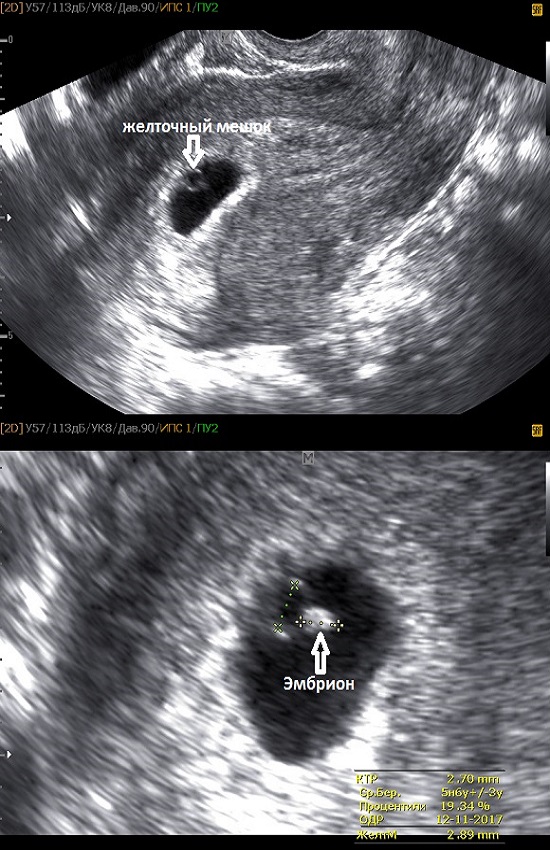

Развитие эмбриона на 8 неделе беременности